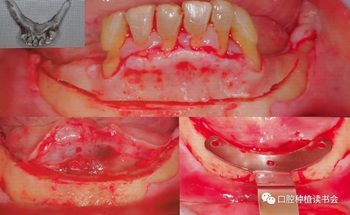

接下來,PauloMalo教授分享了幾個高難度的案例,在重度萎縮的上頜種植患者中采用全螺紋、自擠壓的種植體系統(tǒng),前牙區(qū)植入到骨面下2mm,采用足夠長度的種植體,確??蛇_(dá)到鼻底區(qū)域皮質(zhì)骨,后牙區(qū)采用穿顴種植。如果不采用這種長度及全螺紋的種植體就無法完成即刻負(fù)荷,簡單縫合后,取模制作臨時義齒,取模的步驟很關(guān)鍵,要在所有開窗印模柱上使用成型塑料連接鋼絲,要使用軟質(zhì)硅橡膠,不要使用過硬的油泥型硅橡膠,在骨質(zhì)極度松軟的患者上,必須使用正確的產(chǎn)品,以獲得滿意的臨床效果(圖3)。

圖3 采用穿顴設(shè)計的上頜ALL-on-4臨床即刻負(fù)重案例